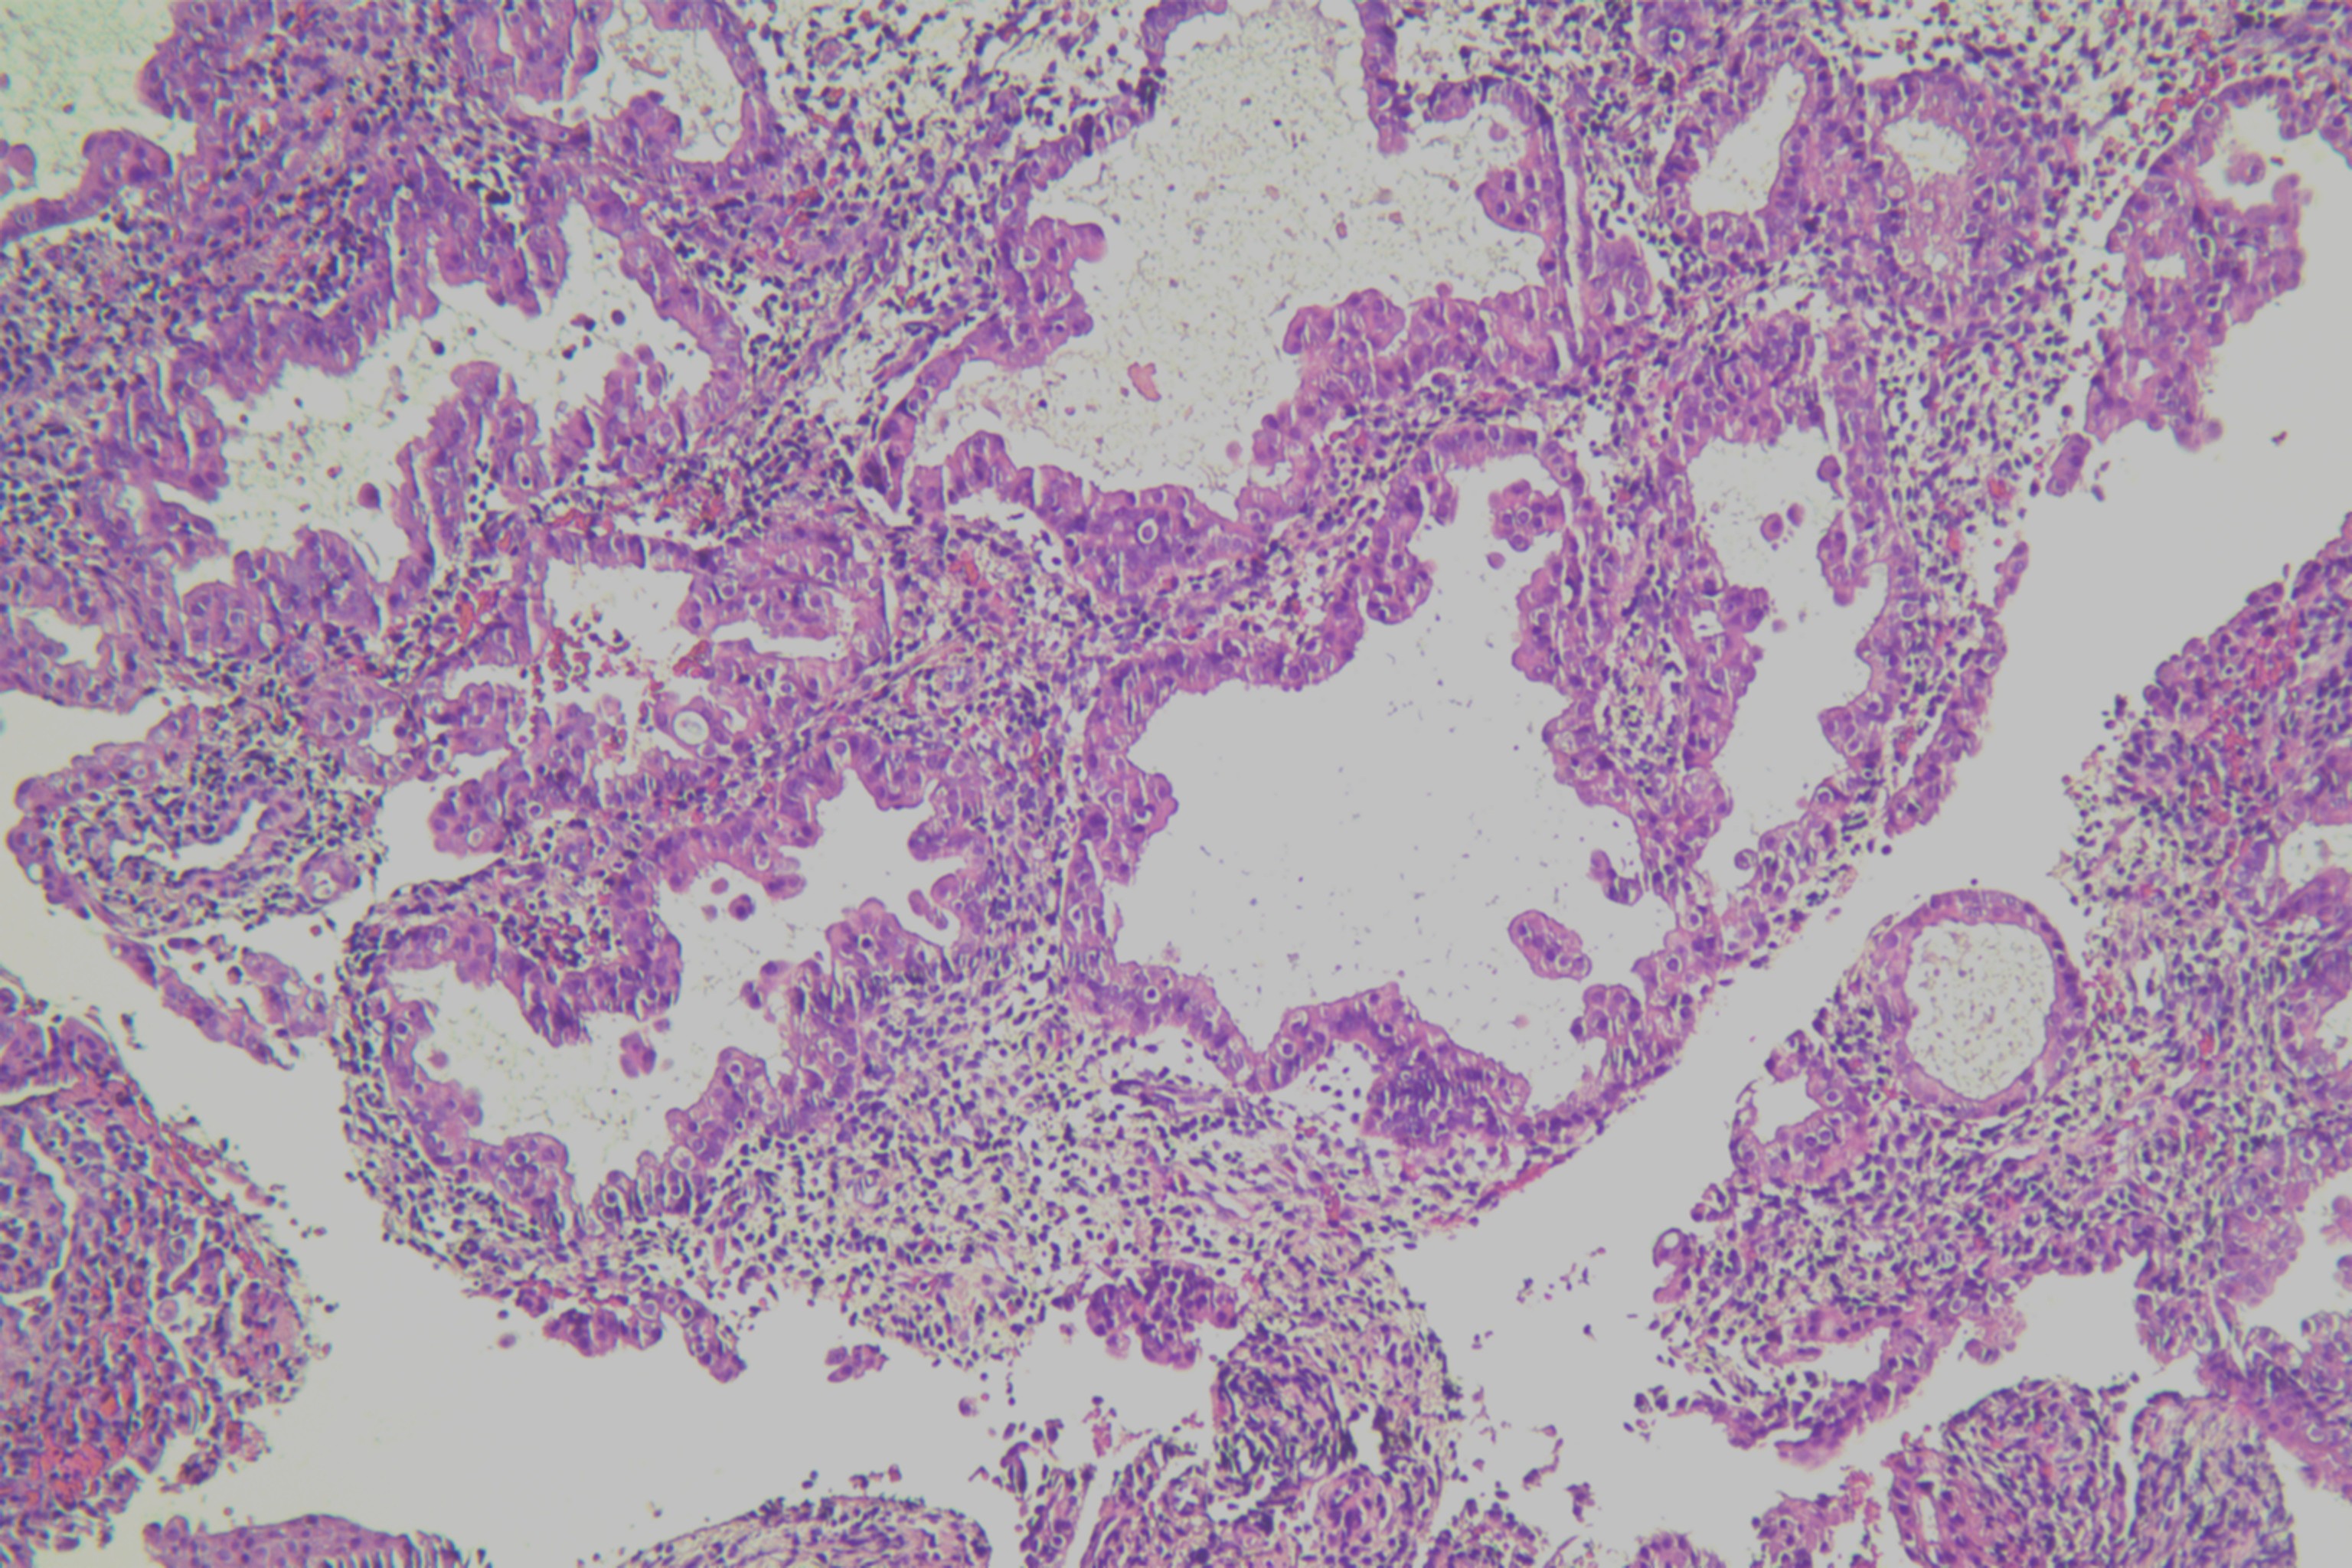

子宫内膜有无非典型性?

月经紊乱1年余,子宫增厚11月

宫腔刮出物

2.8*2.3*0.5cm灰红碎组织一堆。

嗜酸性乳头状化生。

未见非典型增生考虑为子宫内膜单纯性增生部分区域腺体呈复杂性增生(图6)伴部分腺体呈嗜酸性乳头状化生

局灶非典型性增生伴嗜酸性乳头状化生